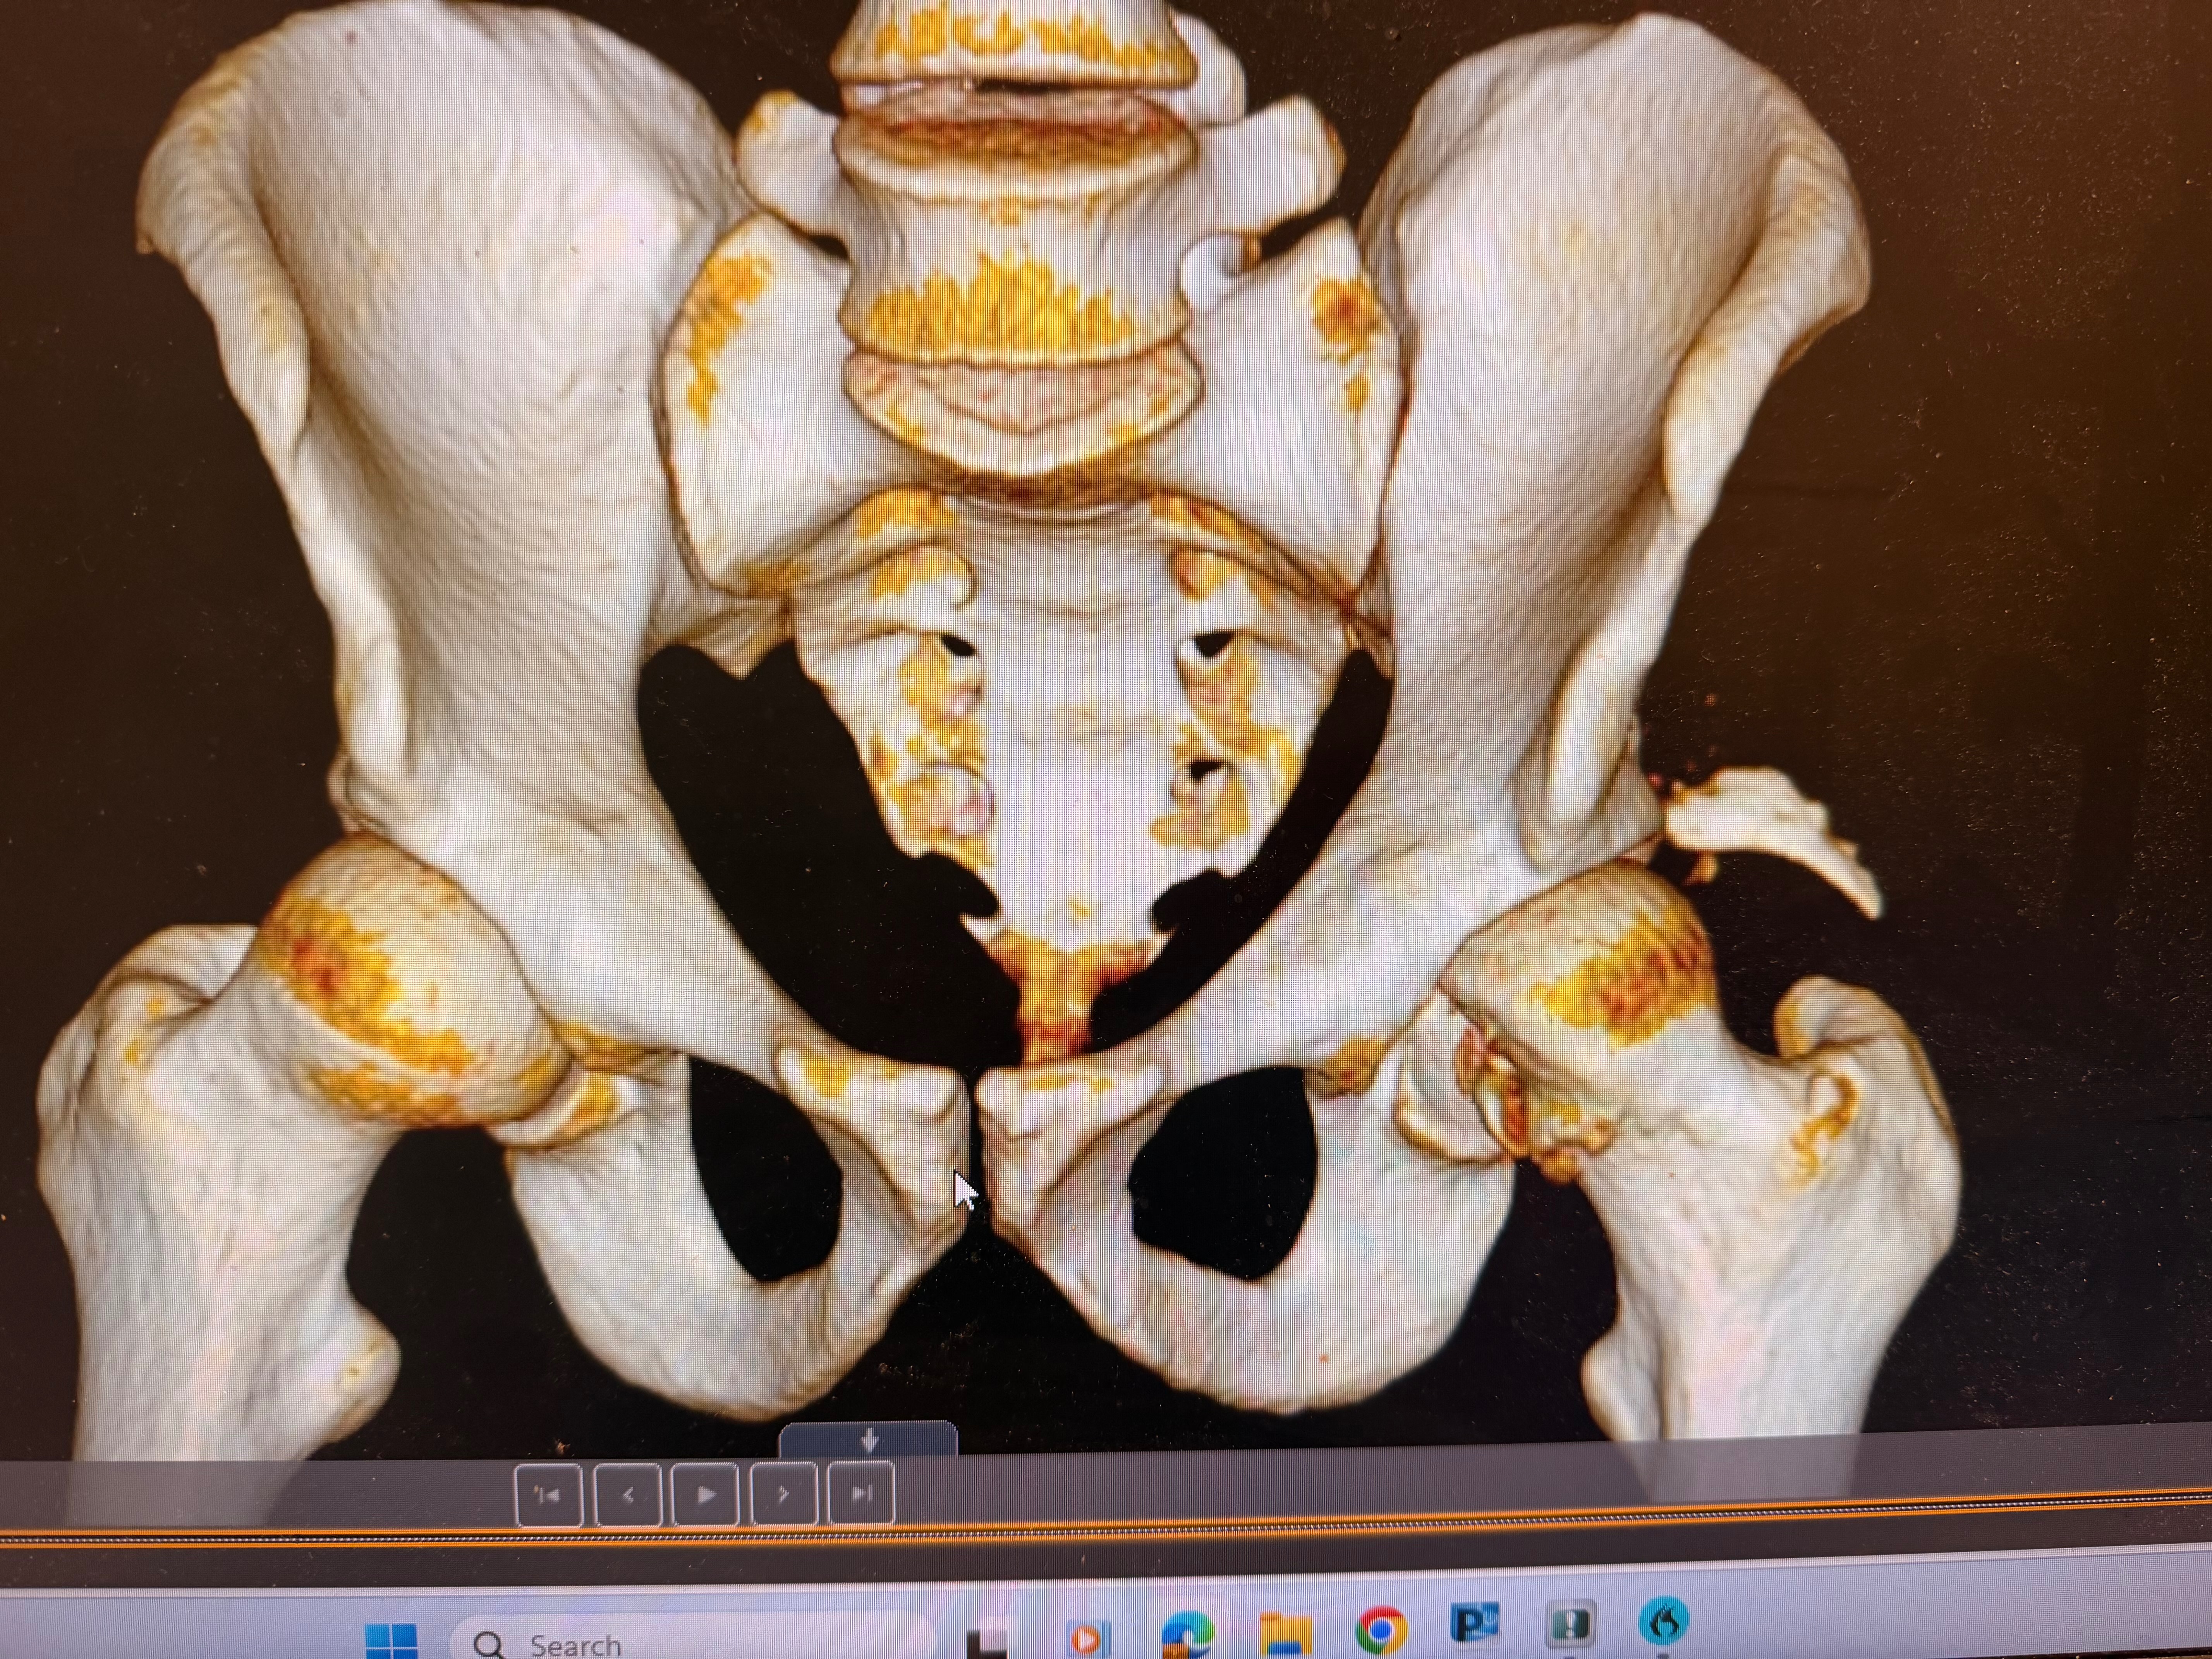

Recently, while training for his upcoming Freestyle Mania tour with Monster Jam, Billy suffered a devastating crash on his home setup. He shattered and dislocated his left hip, fractured his pelvis, and severed his sciatic nerve, leaving him with no mobility in his left foot. The road to recovery is long—doctors estimate 8 to 12 months—and during this time, Billy is unable to work. With no income, he’s facing mounting medical bills and the daily expenses of supporting Willow.